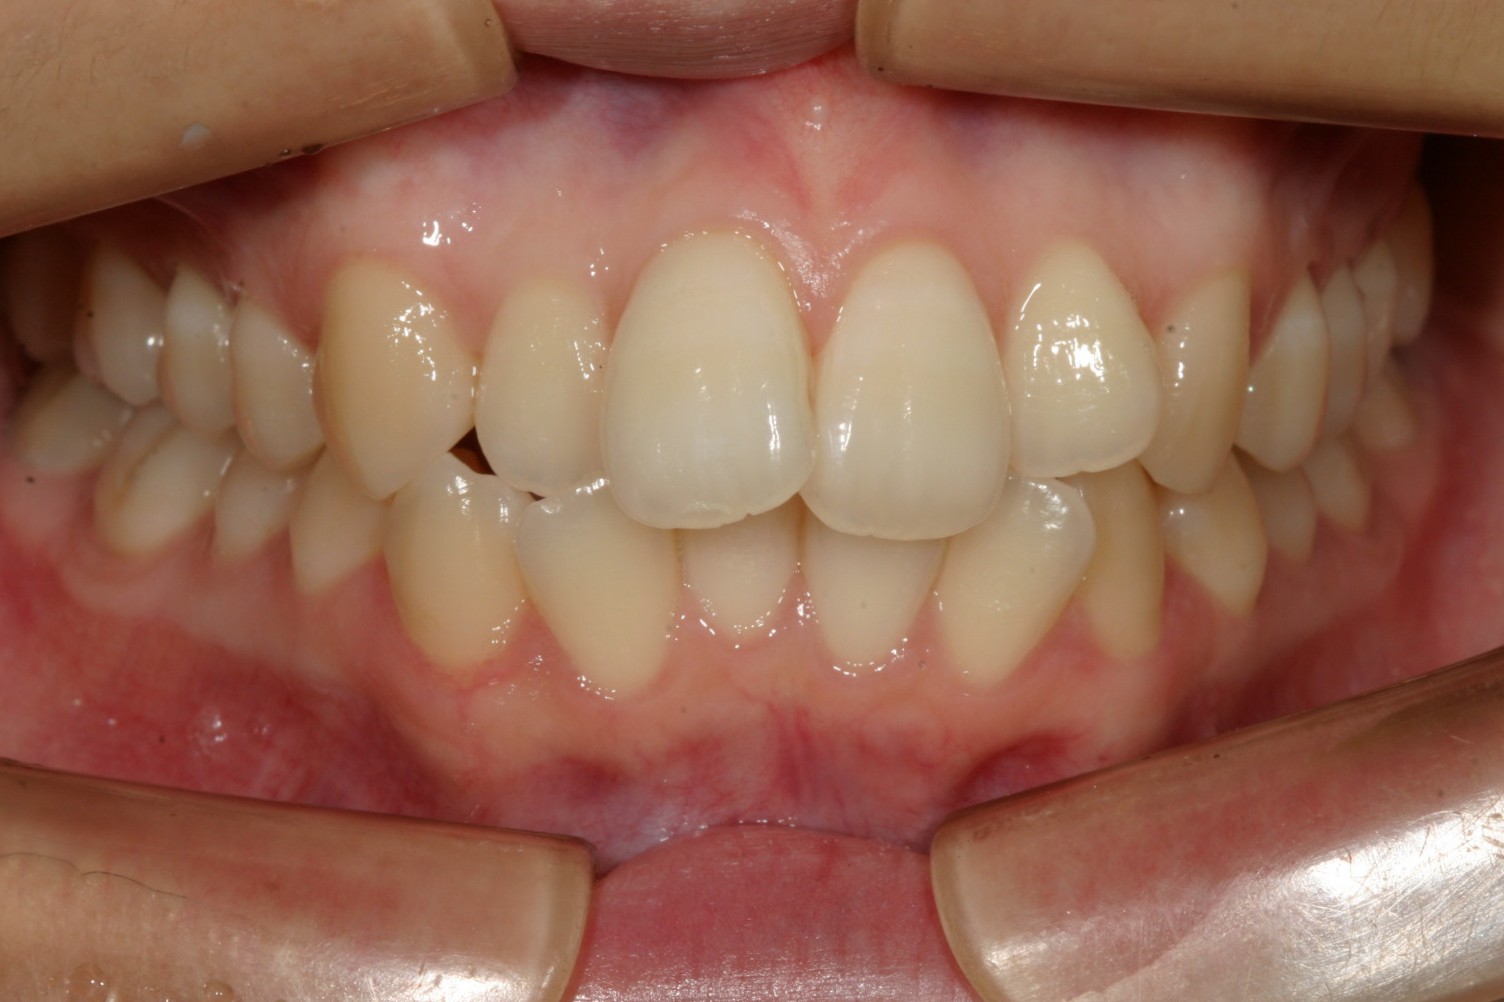

前歯が飛び出てガタガタしてますね。

アーチがV字型な為に前歯が上手く並ばずガタガタしています。

横から見ると上の前歯が突出していますね。